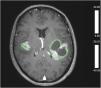

Multiple lesion glioblastoma (M-GBM) represent a group of GBM patients in which there exist multiple foci of tumor enhancement. The prognosis is poorer than that of single-lesion GBM patients, but this actually is a controversial data. Is unknown whether multifocality has a genetic and molecular basis. Our specific aim is to identify the molecular characteristics of M-GBM by performing a comprehensive multidimensional analysis.

ResultsA total of 177 patients were included in the final cohort, 12 patients had M-GBM and 165 patients had S-GBM. Although patients with M-GBM had higher tumor volumes and midline location, the EOR was not different between both type of lesions. Higher percentage of tumors with EGFR overexpression was detected in M-GBM. PFS and OS was significantly shorter in M-GBM.